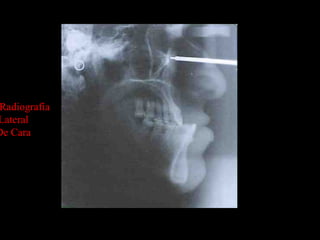

Radiografía

Lateral

De Cara